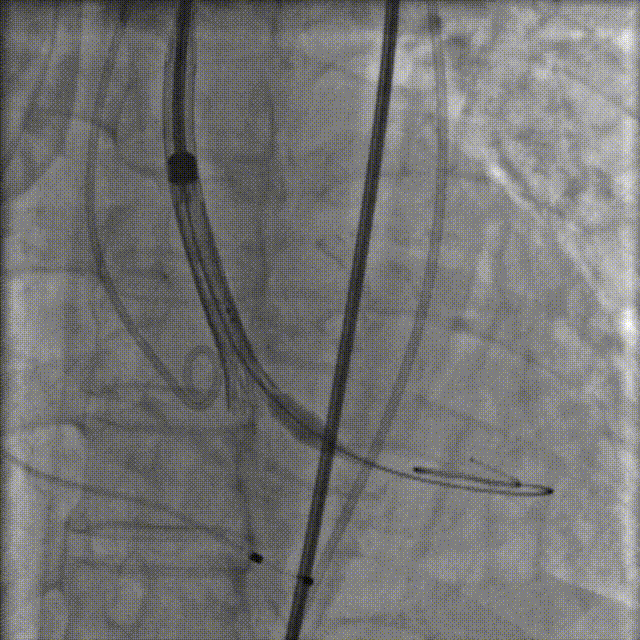

TaurusNXT植入过程

手术采用20mm Z-Med II球囊进行预扩张,植入AV23 TaurusNXT主动脉瓣。在左右重合位影像(cusp overlap view)下释放瓣膜达到工作位,造影显示锚定位置理想,快速释放到回收极限位后在右窦中心位(coplanar view)下再次确认植入位置,同时超声评价瓣膜位置及血流动力学情况,确认无误后精准缓慢释放瓣膜。术后即刻超声心动图评估显示瓣膜位置良好,无瓣周漏,主动脉狭窄及反流均完全解除,主动脉瓣口峰值流速为1.89m/s,平均跨瓣压差为8mmHg,有效瓣口面积为2.01cm²,血流动力学指标理想,未再进行球囊后扩张,整个手术时间仅耗时1小时。

球囊预扩张